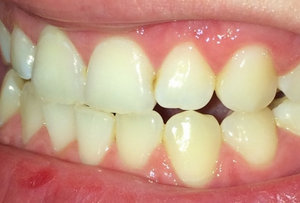

Разошлось мнение двух врачей: одна считает, что кариес на шестнадцатом есть, вторая, что его нет. На рентгене, на шестнадцатом виден темный участок, то есть, скорее кариес есть, чем его нет.

С вашей точки зрения он скорее есть, чем его нет? (речь идет не о поверхностном кариесе, который на рентгене нельзя увидеть, а о более глубоком: среднем или глубоком). Снимок был сделан до лечения.